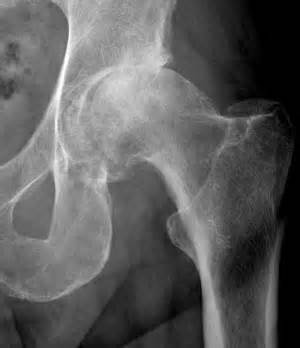

Radiographic signs in the hip of decreased superolateral joint space with sclerosis

DJD of Hip